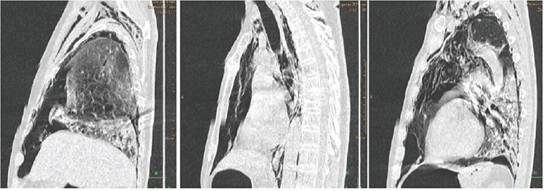

Debido a esto se decide tomografía urgente de control, la cual mostró un neumotórax bilateral de grado moderado asociado a un importante neumomediastino, enfisema subcutáneo en partes blandas de cuello y regiones escapulares, colapso parcial no mayor al 70% de ambos pulmones y la persistencia de infiltrados intersticio-acinares con tendencia a consolidación en bases pulmonares (Ver Figura 1, 2 y 3). Por todo lo anterior se decidió la colocación de sondas torácicas bilaterales inmediatamente. Ante el cuadro progresivo desfavorable que demostró el paciente, se realiza valoración por unidad de cuidados intensivos y durante el traslado al mismo llega a fallecer.